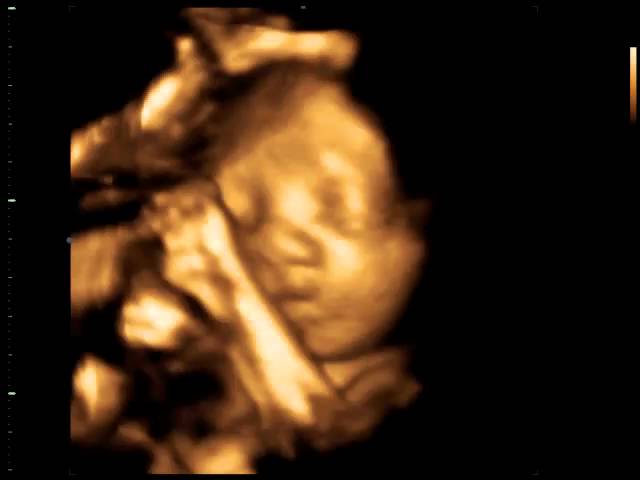

Ambas mostram detalhes do bebê, tais como contornos e fisionomias. A 4D permite ver o bebê em movimento, sorrindo, bocejando, passando a mão no rosto, abrindo e fechando as mãos entre outras peripécias.

Atualmente, disponibilizamos de tecnologia capaz de oferecer imagens tão reais dos bebês que podemos dizer com quem eles se parecem mesmo antes de nascerem. Podemos acompanhar com detalhes cada passo da formação de uma nova vida.